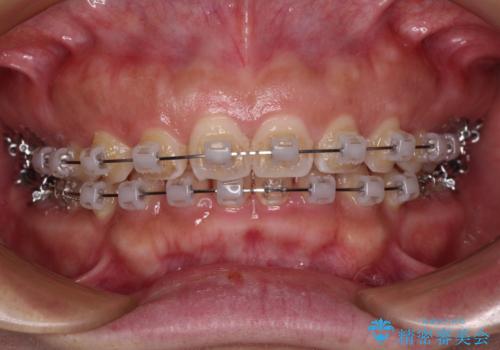

- クリアブラケット

- 2年1ヶ月

手前に傾斜している奥歯を直立させながら、歯列全体の平面を均一に整えることでディープバイトを改善していくこととしました。

ディープバイトは咬合力が強いことが特徴であり、より良い仕上がりとするために、臼歯部のコントロールを行いやすいワイヤー装置を用いて矯正治療を行うこととしました。